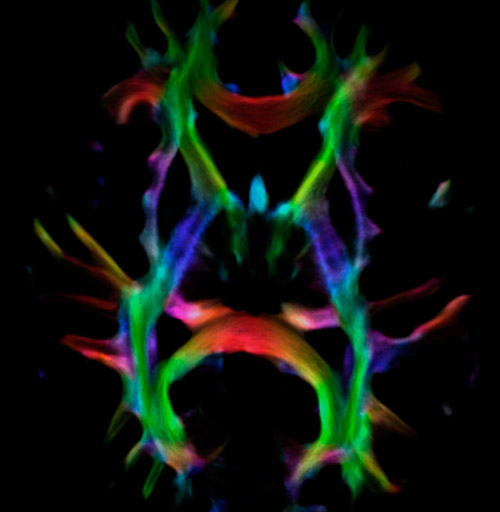

Fiber orientation density

CSD of multishell DWI results in the white matter FOD at each voxel. Unlike the conventional diffusion tensor model, this approach enables accurate modeling of multiple fiber populations within a single voxel.

UVM research fiber orientation density

Crossings of the corpus callosum, corticospinal tracts, and the superior longitudinal fasciculus are shown.

Crossing fibers of the corpus callosum bordered by the superior longitudinal fasciculus as well as within in the pons.